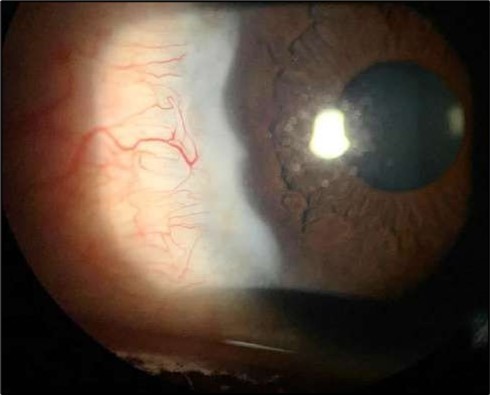

At six-months follow-up post-resection, the ulcer showed progressive epithelialization with no recurrence. Oral prednisolone was gradually tapered and stopped. The patient remains under regular ophthalmology follow-up with stable ocular findings Figure 6.

Figure 6.Six-month follow-up image showing a stable ocular surface, and absence of ulcer recurrence. The cornea appears clear centrally, with stromal scarring limited to the periphery.